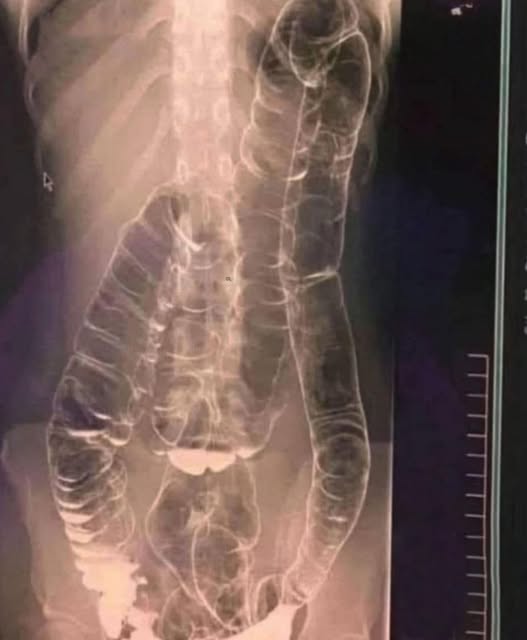

A recent case perfectly illustrates this phenomenon. A patient who had gone nearly two weeks without normal bowel movements underwent a revealing examination. The X-ray showed an abnormally dilated colon, extending up to the chest, clogged with fecal matter that had hardened like concrete.

Illustration of a distended colon

Consider the example of a balloon that is continually filled without ever being emptied. This is what happens with an overloaded colon: its elasticity gradually decreases, reducing its ability to propel waste toward the exit. A vicious circle then sets in—the longer constipation persists, the more problematic evacuation becomes.